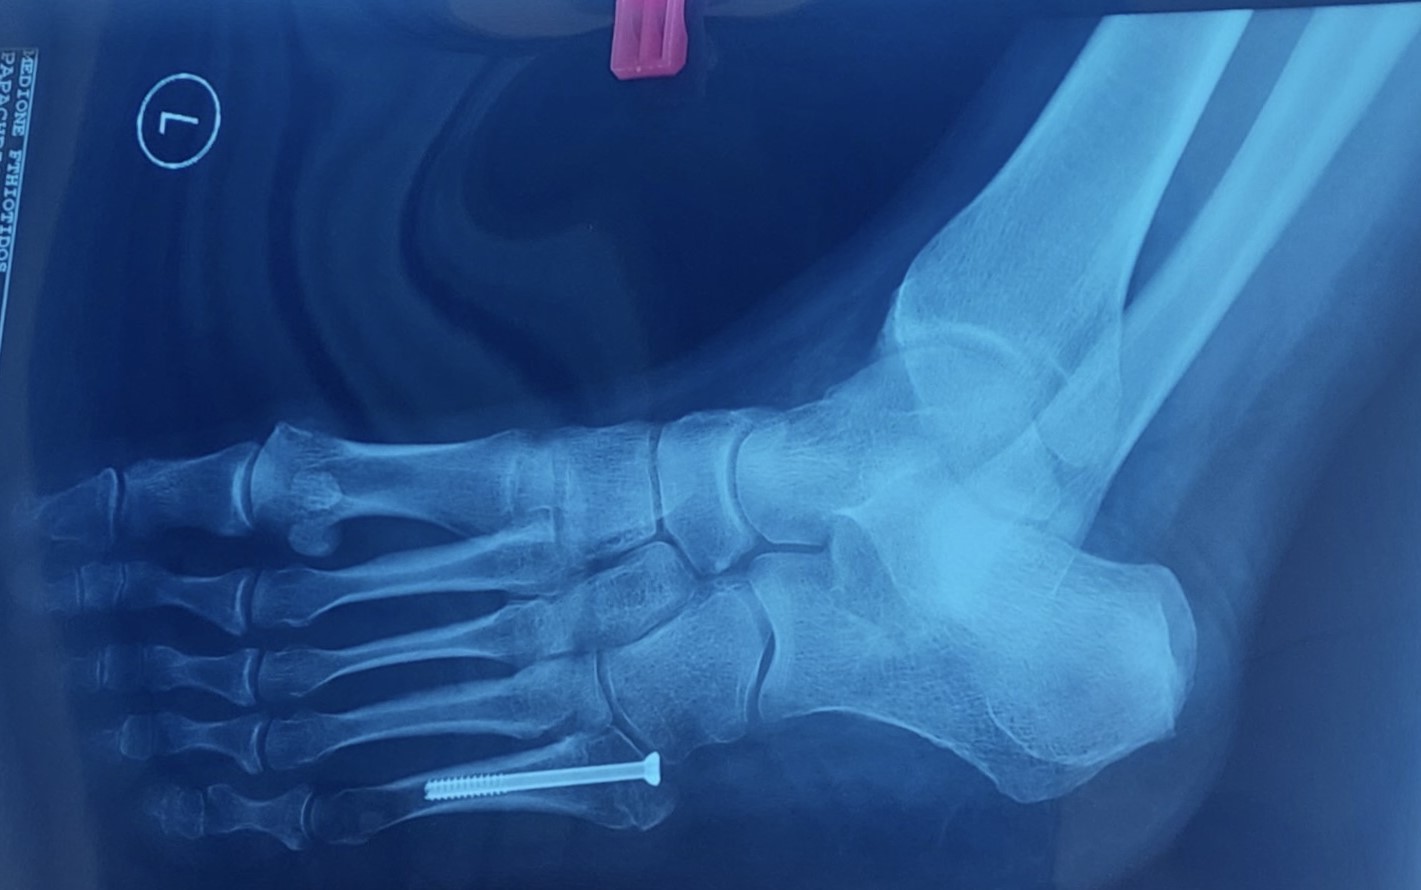

Όπως σε κάθε τραυματισμό, η επίσκεψη σε έναν έμπειρο Ορθοπαιδικό είναι απαραίτητη. Αρχικά, ο ιατρός λαμβάνει το ιστορικό του ασθενούς και στη συνέχεια προχωρά στην κλινική εξέτασή του. Στην συνέχεια, μια απλή ακτινγραφία είναι συνήθως αρκετή για τη διάγνωση του κατάγματος. Υπάρχουν όμως και περιπτώσεις όπου για τον εντοπισμό του κατάγματος Jones μπορεί να είναι απαραίτητη η διενέργεια αξονικής ή μαγνητικής τομογραφίας.

Η μέθοδος οστεοσύνθεσης ενός κατάγματος Jones συνίσταται στην τοποθέτηση ενός ενδομυελικού κοχλία, διαδερμικά. Η επάνοδος του ασθενούς στις καθημερινές και στις αθλητικές του δραστηριότητες επιτυγχάνεται στο μικρότερο χρονικό διάστημα.